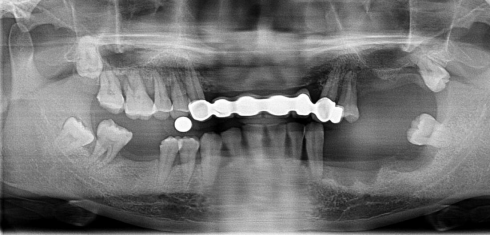

不連續(xù)性牙缺失修復(fù)案例

53歲的周女士家住福州晉安,由于患有嚴(yán)重的牙周炎導(dǎo)致牙齒沒剩下幾顆了。

“這邊缺一顆,那邊缺幾顆,這咬東西也太不得勁了,有牙齒跟沒牙齒一樣。”周女士深知牙齒缺失的痛苦,但是卻因?yàn)榻?jīng)濟(jì)的原因一直拖延沒有進(jìn)行牙齒修復(fù):“做牙齒多貴了,一顆就幾萬塊哪里舍的。”

錢雖然重要但缺失牙確實(shí)痛苦。而近期周女士又湊巧在報(bào)紙上看到科爾口腔的“敬業(yè)福”公益活動(dòng)的消息,一顆牙齒可以免費(fèi)領(lǐng)取4000元的種植牙紅包,優(yōu)惠力度之大前所未有,種植5顆還可以省下幾萬塊。

周女士來院與劉斌元教授進(jìn)行交流后,劉斌元教授表示:“周女士缺失的牙齒是非連續(xù)性的,因此要種上好幾顆。牙齒缺失千萬不可掉以輕心,長(zhǎng)時(shí)間缺失牙齒可造成牙槽骨萎縮,還會(huì)影響相鄰牙齒健康狀況”